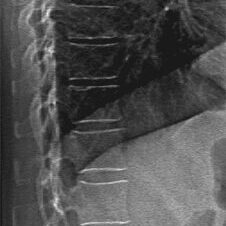

Provides Axial Scan capability which includes hip and lumbar spine. The forearm is scanned in patients with bilateral hip replacement or lumbar surgery.

Instant Vertebral Assessment Scans (IVA) to assess fracture risk and identify spine fractures by combining bone density with high-resolution vertebral imaging. (Thoracic compressions only)